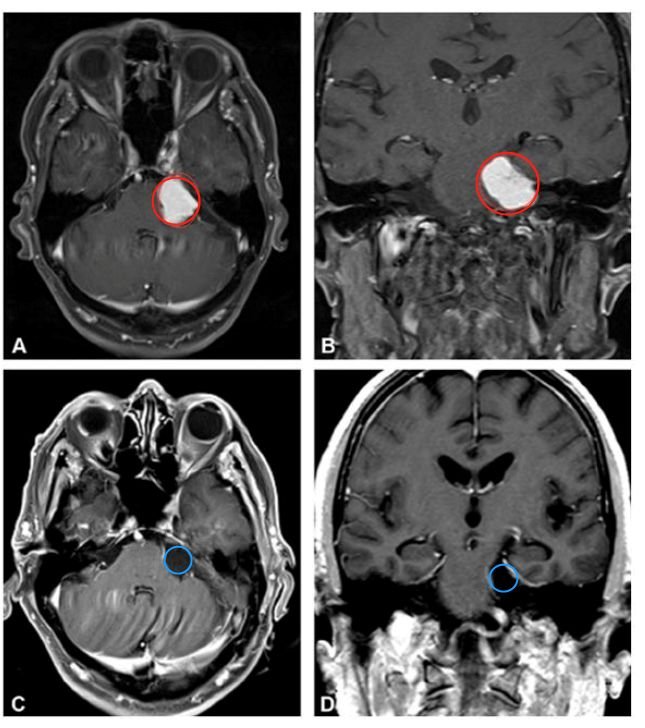

术前MRI:从脑幕下表面向左小脑桥脑角产生大的均匀增强病变,引起显著的脑干压迫,出现面部麻木和步态失衡

诊断:桥小脑角区脑膜瘤

手术方案:左侧乙状窦后开颅手术切除肿瘤

术后情况:手术顺利,脑膜瘤得以全切,没有新的术后神经功能缺损,脑干压迫消失。术后第4天出院回家,术后1个月,步态失衡和左侧面部麻木消失。其后到现在的4年间,随访未见脑膜瘤复发,老人一切生活正常。

(A、B为术前影像,C、D表示术后影像)